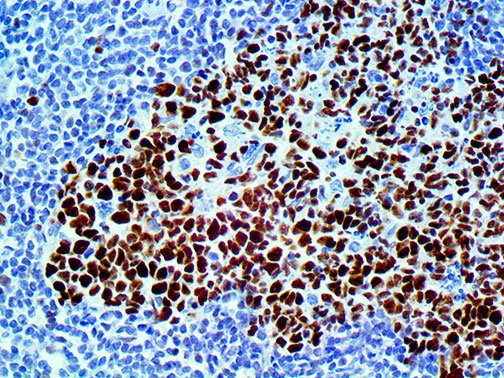

The first cytokines released are interleukin 1β (IL-1β) and tumor necrosis factor-α (TNF-α), which attract a variety of circulating white blood cells (WBCs) to the infection site, including neutrophils, monocytes, macrophages, and natural killer (NK) cells. This response, along with the antipathogenic chemicals released by these cells (i.e., complement), comprise the innate immune response. These cells directly attack the invading pathogen and also release additional cytokines, chief among them interleukin-1 and 6 (IL-6). IL-6 is essential for invoking the adaptive immune response, which calls T-cells, B-cells, and T helper (Th) cells to the infection site. IL-6 also stimulates further recruitment, proliferation and activation of macrophages.

It is the ICU physician who is most likely to witness one of the deadliest manifestations of the abnormal immunological response, the cytokine storm syndrome (CSS). This response is also referred to by some as the cytokine release syndrome (CRS). CSS is characterized by continuous activation and expansion of macrophage and lymphocyte populations, which secrete large amounts of cytokines, causing the cytokine storm. This massive cytokine release is akin to hemophagocytic lymphohistiocytosis (HLH) disease, a syndrome characterized by initial unchecked and persistent activation of cytotoxic T lymphocytes and NK cells.

Clinical and laboratory manifestations of HLH include fever, enlarged liver and/or spleen, neurologic dysfunction, coagulopathy, liver dysfunction, cytopenias (i.e., low levels of erythrocytes, leukocytes, and/or platelets), hypertriglyceridemia, hyperferritinemia, hemophagocytosis, and eventually diminished NK cell activity as the immune system becomes progressively paralyzed. HLH can be familial (primary HLH) or secondary to another disease process (sHLH), such as rheumatic disease, in which it is referred to as macrophage activation syndrome (MAS, characterized by elevated ferritin).